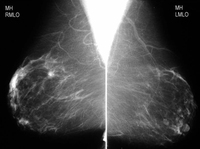

Screening mammogram demonstrating breast mass

Courtesy of Dr Nancy Pile, University of Louisville; used with permission